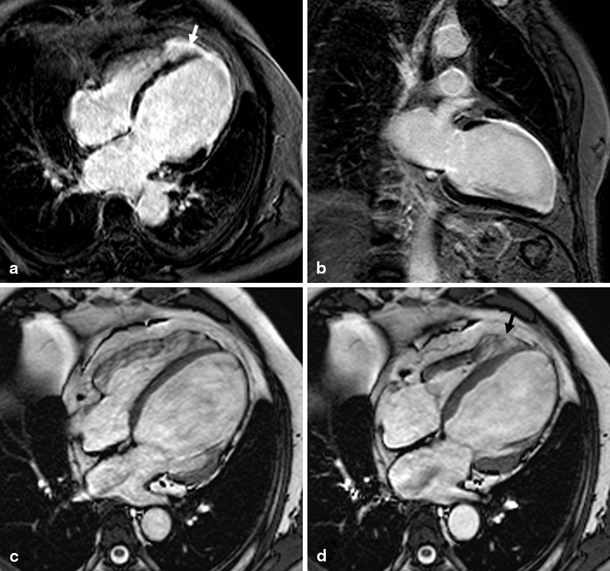

The RVEF was more impaired and RV size larger in patients with DCM in comparison with patients with IHD (Figs. 3 and 4) despite similar LV systolic and diastolic dysfunction. There was an isolated increase in E/e’ of the septum in DCM patients, but an opposite trend laterally and no further differences were seen in diastolic parameters between the groups, suggesting no difference in diastolic LV function. LV EDV and ESV were not different between the groups. All CMR and echocardiography parameters are summarised in Table 1.

Fig. 4

Late gadolinium enhancement (a, b) and cine (four-chamber view in end-diastole (c) and end-systole (d)) magnetic resonance images of a patient with idiopathic dilated cardiomyopathy with more pronounced dilation of the right ventricle (left ventricular ejection fraction 36 %, end-diastolic volume 211 ml; right ventricular ejection fraction 23 %, end-diastolic volume 269 ml) Although elevated left ventricular filling pressure and TI velocity were present, the degree of right ventricular dilation is out of proportion, possibly suggesting an active unknown process affecting the right ventricle more than the left ventricle